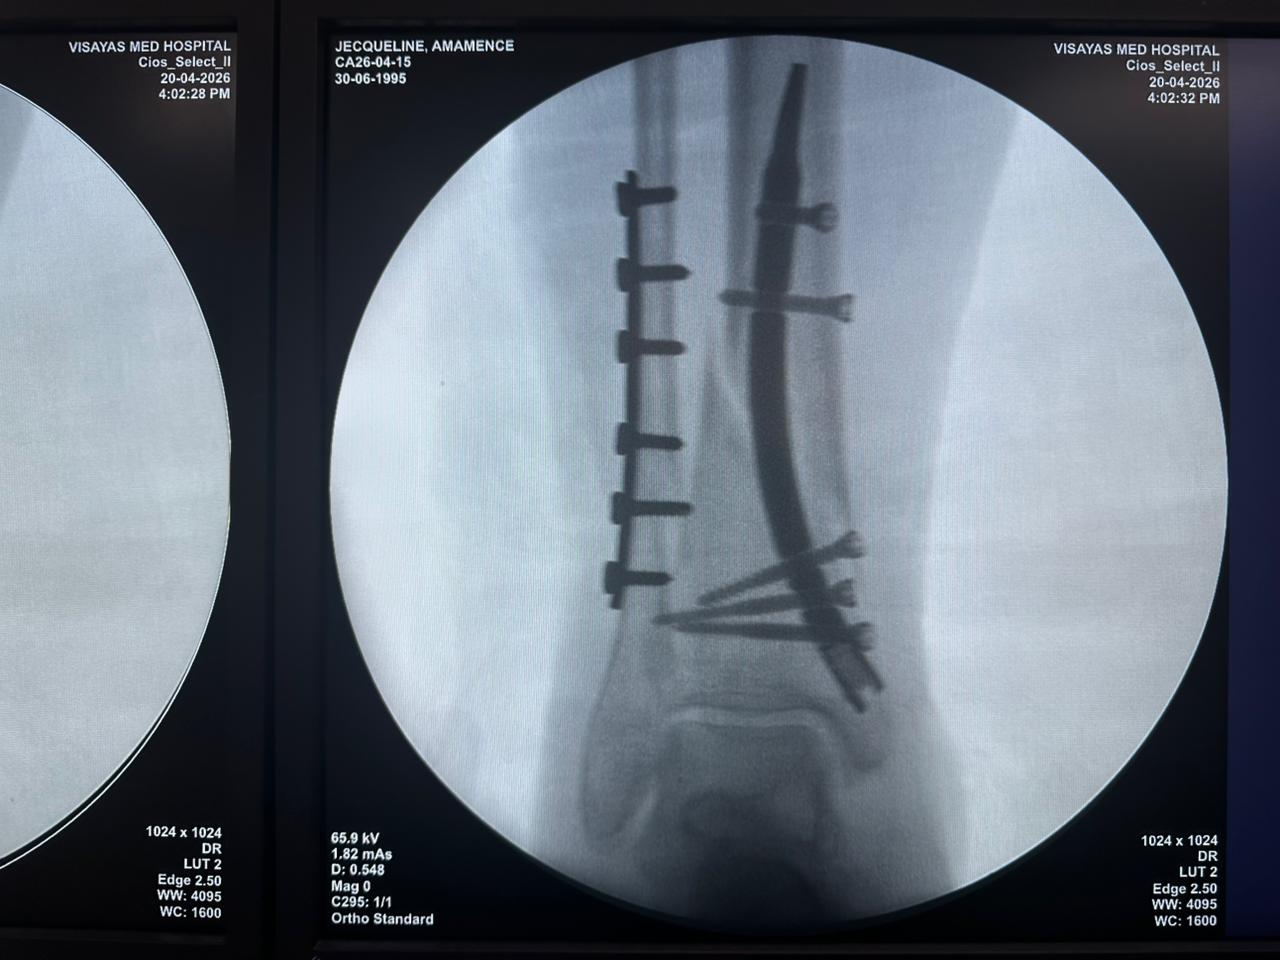

Estudio de caso de fijación de clavo tibial distal con soporte de placa para peroné

Tibia y peroné distales

Clavo tibial distal

Placa de bloqueo del peroné

Radioscopia intraoperatoria con arco en C, vistas AP y lateral

Este caso involucró la fijación de la tibia distal utilizando un clavo tibial distal intramedular. La fluoroscopia intraoperatoria confirmó la posición del clavo, los tornillos de bloqueo distales y la fijación de la placa del peroné.

caso-de-fijación-de-tibia-distal-peroné-CZMEDITECH